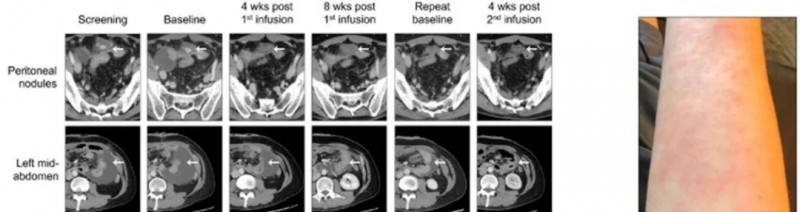

2021 年 5 月,M先生参加了CT-041 CAR-T细胞疗法在美国进行的临床试验,第一次CAR-T细胞回输后,他可以吃一些固体食物,并在约 5 个月后首次进行直肠排便。第二次回输后仅4 周,M先生的影像检查结果显示肿瘤靶病灶竟然全部消失,达到了完全缓解(CR),并且脾周结节和胃壁增厚完全消退,更让人无法相信的是,血液层面追踪体内残存细胞的ctDNA 检测结果显示为阴性,这意味着M先生体内已经没有分子残留疾病(MRD)!而且第二次回输M先生没有皮疹,他的精力水平显著提高,使他能够独立照顾孩子。在第一次 CT041 输注后 8 个月,M先生持续处于完全缓解状态!这也是海外报道的首例Claudin18.2 CAR-T治疗后达到完全缓解的胃癌患者!

在预处理化疗后接受了第一次6亿个CT041细胞的治疗,影像显示肿瘤大小分别减小了19.2%、24.4%和26.9%。首次回输三个月后,患者接受了第二次6亿个CT041细胞的输注。CT扫描显示,与基线相比,肿瘤持续缩小,分别减小了34.6%(首次输注后4个月)和41.0%(首次输注后5个月)。